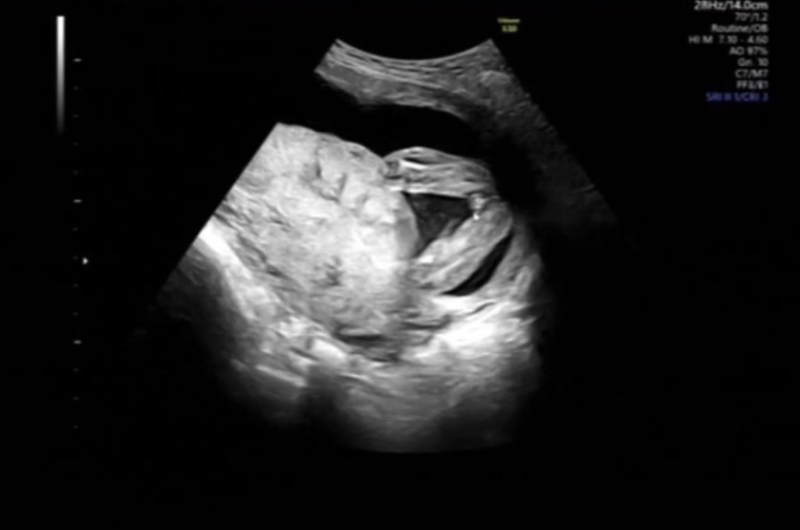

せっかくご質問いただきましたが、こちらのエコーの写真だけで、性別を判断するのは困難でした。

また、性別に関しては、お答えすることに際しまして、間違いがあってもよくないので、控えさせていただいております。